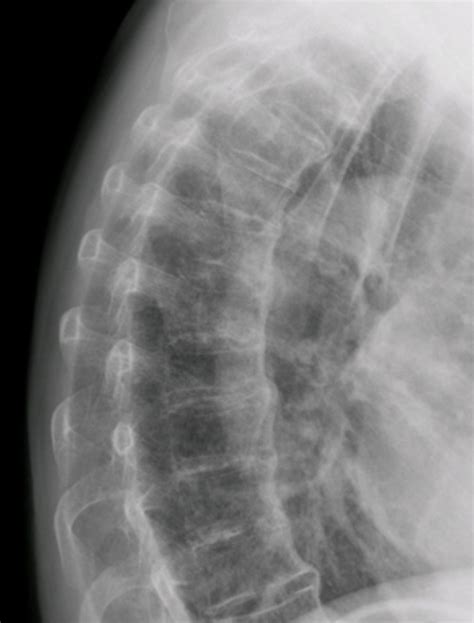

Okay, so how do doctors actually see these thoracic spurs ? That’s where X-rays come in. An X-ray is a type of imaging test that uses a small amount of radiation to create pictures of the inside of your body. When you get a chest or spine X-ray, the technician will position you in front of the machine, and the X-ray beams will pass through your body. The bones absorb some of the radiation, which allows the machine to create a detailed image. On the X-ray, bone spurs will appear as small, extra bony growths along the edges of the vertebrae. They usually look like tiny spikes or bumps. Your doctor will carefully examine the X-ray to identify the presence, size, and location of any spurs.

X-ray imaging is a valuable diagnostic tool for detecting thoracic spurs. The process involves a technician positioning you in front of the X-ray machine so that the beams can pass through your body. The bones absorb some of the radiation, creating a visual image. This image allows medical professionals to identify the presence, size, and location of any bone spurs. On an X-ray, bone spurs are typically seen as small, additional bony growths along the edges of the vertebrae. They often appear as tiny spikes or bumps, which are easily distinguishable from the normal bone structure. The clarity of the image allows doctors to evaluate the severity of the condition and make accurate diagnoses. The doctor examines the X-ray carefully to note any irregularities. These images are essential in helping doctors understand the extent of the condition and plan appropriate treatment. For example, if spurs are compressing nerves or causing other issues, the X-ray provides vital information to guide further investigations or treatment decisions. In addition to detecting bone spurs, X-rays can also help rule out other potential causes of back pain, making them a crucial part of the diagnostic process. This detailed process is important for accurately identifying and assessing the condition of the thoracic spine. This is essential for proper diagnosis and management.

When the X-ray is interpreted, doctors look for specific signs. The key is to look for the characteristic appearances of the spurs. They evaluate the size, shape, and location of the spurs to understand their impact. The number of spurs and their locations are important factors. The presence of other spinal issues such as degeneration, is noted. The alignment of the spine is assessed to evaluate whether the spurs affect posture or movement. The density of the bone is also checked, as this can give clues about the overall health of the spine. When analyzing, the doctors also consider the patient’s symptoms and medical history. This comprehensive approach is essential for accurate diagnoses and effective treatment plans. Proper interpretation ensures that the condition is managed effectively.